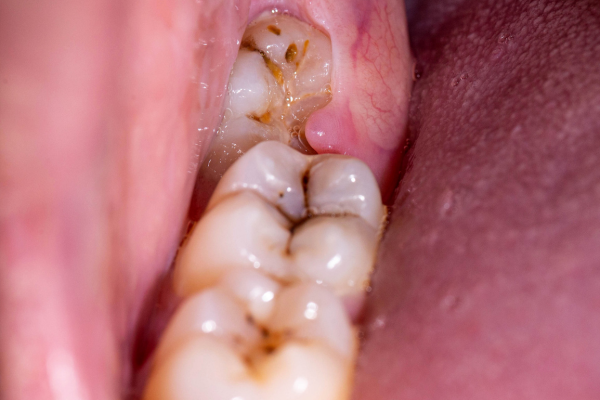

An impacted wisdom tooth.

Infection (pericoronitis) – when an impacted tooth breaks through the surface of the gums, it can allow bacteria in and cause an infection that may result in severe pain, swelling, jaw stiffness, and even general illness.

Destruction of the next tooth – the tooth may try to grow where it has no room, eroding the tooth next to it (called resorption).

Pain – an impacted tooth may press against a nerve or the next tooth, causing pain. Infection in a decayed tooth or the gums may also cause pain.